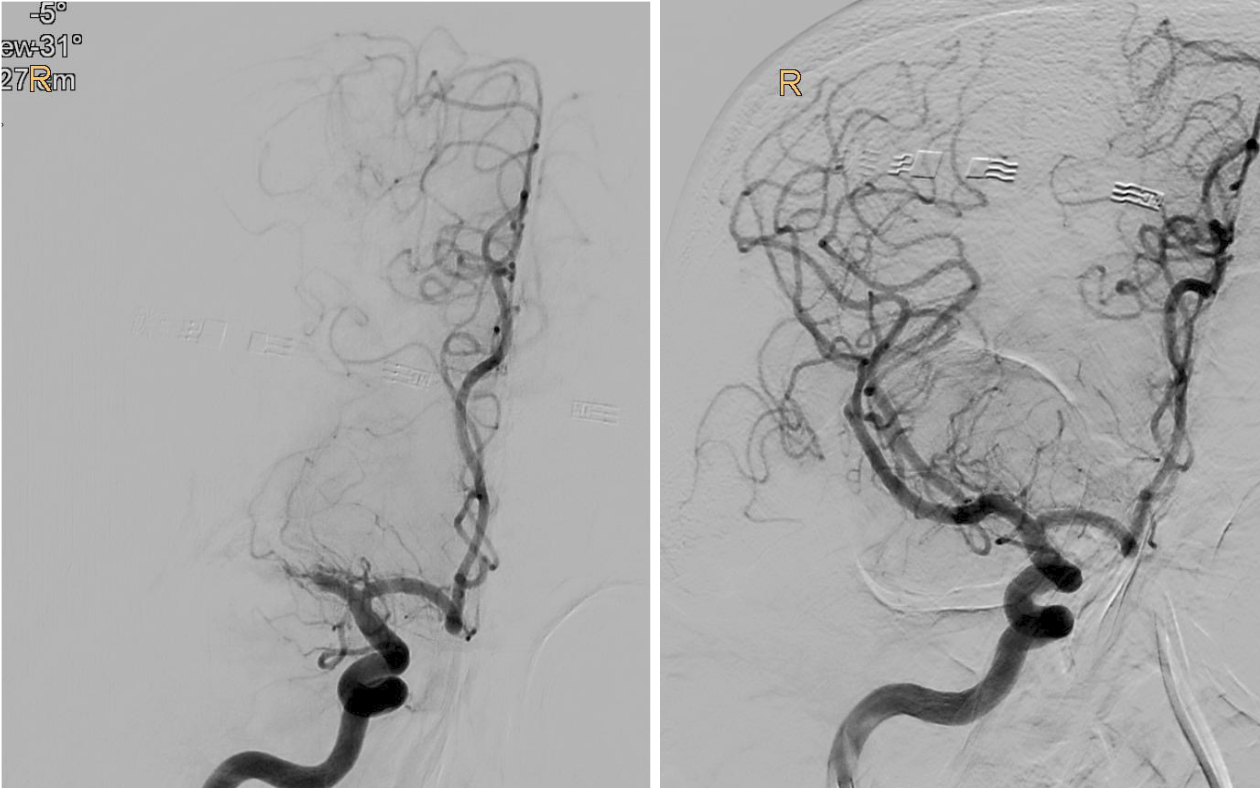

BU: Verschluss des mittleren Hirngefäßes in der Angiographie dargestellt (l.), und wieder eröffnet (r.). Bilder: Univ.-Klinik für Radiologie

„Bei der Thrombektomie bringen wir mit einem Spezialkatheter von der Leiste ausgehend einen Stent an der Stelle des Gehirns ein, wo das Gerinnsel sitzt. Mit einer Saugvorrichtung wird das Blutgerinnsel dann zusammen mit dem Stent herausgezogen. Das Ganze passiert unter Röntgenkontrolle und bedarf viel Erfahrung“, erklärt Gizewski den sensiblen Vorgang.

Vor 2015 wurde eine Thrombektomie standardmäßig meist nur durchgeführt, wenn eine Thrombolyse – medikamentöse Auflösung des Gerinnsels – bei den jeweiligen Patient:innen nicht durchgeführt werden konnte. Die großen Studien 2015 konnten zeigen, dass Patient:innen im frühen Stadium sehr von der Thrombektomie profitieren. Im Zuge der TENSION-Studie untersuchten die Expert:innen nun die Effektivität der Thrombektomie bei Schlaganfall-Patient:innen, deren Gehirn schon schwer geschädigt war.

„Bei einem Schlaganfall zählen einerseits Zeit und andererseits die noch verbliebene Sauerstoffversorgung des Gehirns, welche bei den Patient:innen unterschiedlich ausfällt. So genannte Kollaterale, Gefäß-Querverbindungen, können die Durchblutung noch einige Zeit aufrechterhalten. Je weniger solcher Kollateralen vorhanden sind, desto weniger Zeit hat man. Doch auch wenn schon Gewebe untergegangen ist, kann man noch etwas retten, wenn man thrombektomiert. Das konnten wir jetzt mit der TENSION-Studie zeigen“, berichtet Gizewski. Viele der Patient:innen könnten trotz der bedrohlichen Ausgangssituation jetzt wieder ein eigenständiges Leben führen. Nachdem sich der Erfolg der Katheter-Behandlung (insgesamt 125 Patient:innen) in der randomisierten Studie im Vergleich zur besten konservativen medizinischen Behandlung (128 Patient:innen) schnell gezeigt hatte, wurde die Studie frühzeitig beendet.